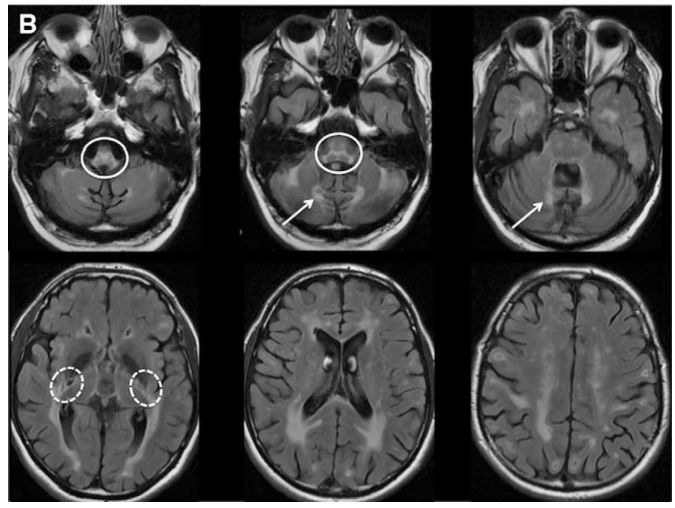

- APBD is a GSD caused by glycogen branching enzyme (GBE) deficiency leading to poorly branched glycogen, called polyglucosan, which precipitate, aggregate, and accumulate into polyglucosan bodies. (Akman et al, 2009; Mochel et al, 2012)

- APBD is affected by mutations in the same gene as Andersen’s disease (GSD type IV) which is characterized by the absence of GBE, this may lead to liver failure and death in childhood. Milder mutations of GBE, as in APBD, lead to smaller polyglucosan bodies, these do not disturb most cell types. In neurons and astrocytes, however, over time polyglucosan bodies plug the tight confines of axons and processes and lead to APBD (Akman et al, 2015)